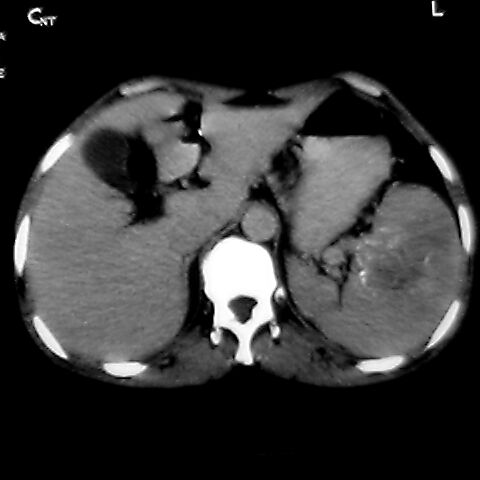

女 48岁 食道癌术前体检发现脾占位。

脾胀内部巨大低密度肿块,边界清或不清,中心坏死,轻度增强,内见散在钙化,结合食道癌病史多考虑:转移癌.

脾脏低密度灶伴钙化,增强化明显,中心见液化坏死灶,强化延时明显。考虑血管瘤。转移瘤待排。

转移瘤不可能单发,考虑脾血管瘤。